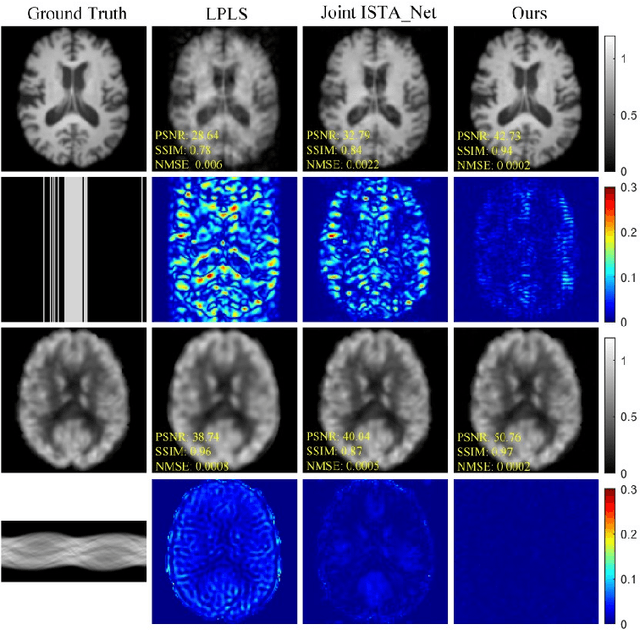

Abstract:Positron Emission Tomography and Magnetic Resonance Imaging (PET-MRI) systems can obtain functional and anatomical scans. PET suffers from a low signal-to-noise ratio. Meanwhile, the k-space data acquisition process in MRI is time-consuming. The study aims to accelerate MRI and enhance PET image quality. Conventional approaches involve the separate reconstruction of each modality within PET-MRI systems. However, there exists complementary information among multi-modal images. The complementary information can contribute to image reconstruction. In this study, we propose a novel PET-MRI joint reconstruction model employing a mutual consistency-driven diffusion mode, namely MC-Diffusion. MC-Diffusion learns the joint probability distribution of PET and MRI for utilizing complementary information. We conducted a series of contrast experiments about LPLS, Joint ISAT-net and MC-Diffusion by the ADNI dataset. The results underscore the qualitative and quantitative improvements achieved by MC-Diffusion, surpassing the state-of-the-art method.